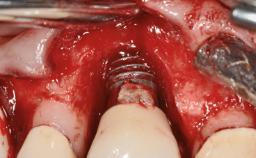

A 30-year-old female patient was referred to the Department of Periodontology of the University of Bern, Switzerland, by a dentist in private practice. Tooth 45 had been congenitally missing and had been replaced with a titanium implant three years prior to the first visit at the Department of Periodontology. The tissue level implant had a diameter of 4.1 mm, a length of 12 mm, and a sandblasted and acid-etched (SLA) surface (Straumann® Dental Implant System; Institut Straumann AG, Basel, Switzerland). The metal-ceramic crown on implant 45 had been cemented permanently. Implant 45 had been diagnosed with peri-implantitis by the referring dentist in the course of regular supportive care.

Peri-implantitis Modified by Submucosal Excess of Cement: Regenerative Peri-implantitis Therapy and Six-year Follow-up